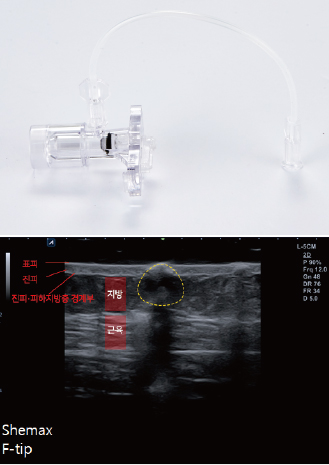

Transcutaneous Pneumatic InjectionSHEMAX uses compressed air pressure to spray liquid medicine instantaneously.

At this time, liquid medicine is delivered to a certain depth through physical energy.